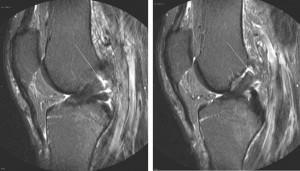

To see pictures of a torn ACL, including before-and-after pictures of ACL reconstruction surgery, please visit our knee arthroscopy gallery.